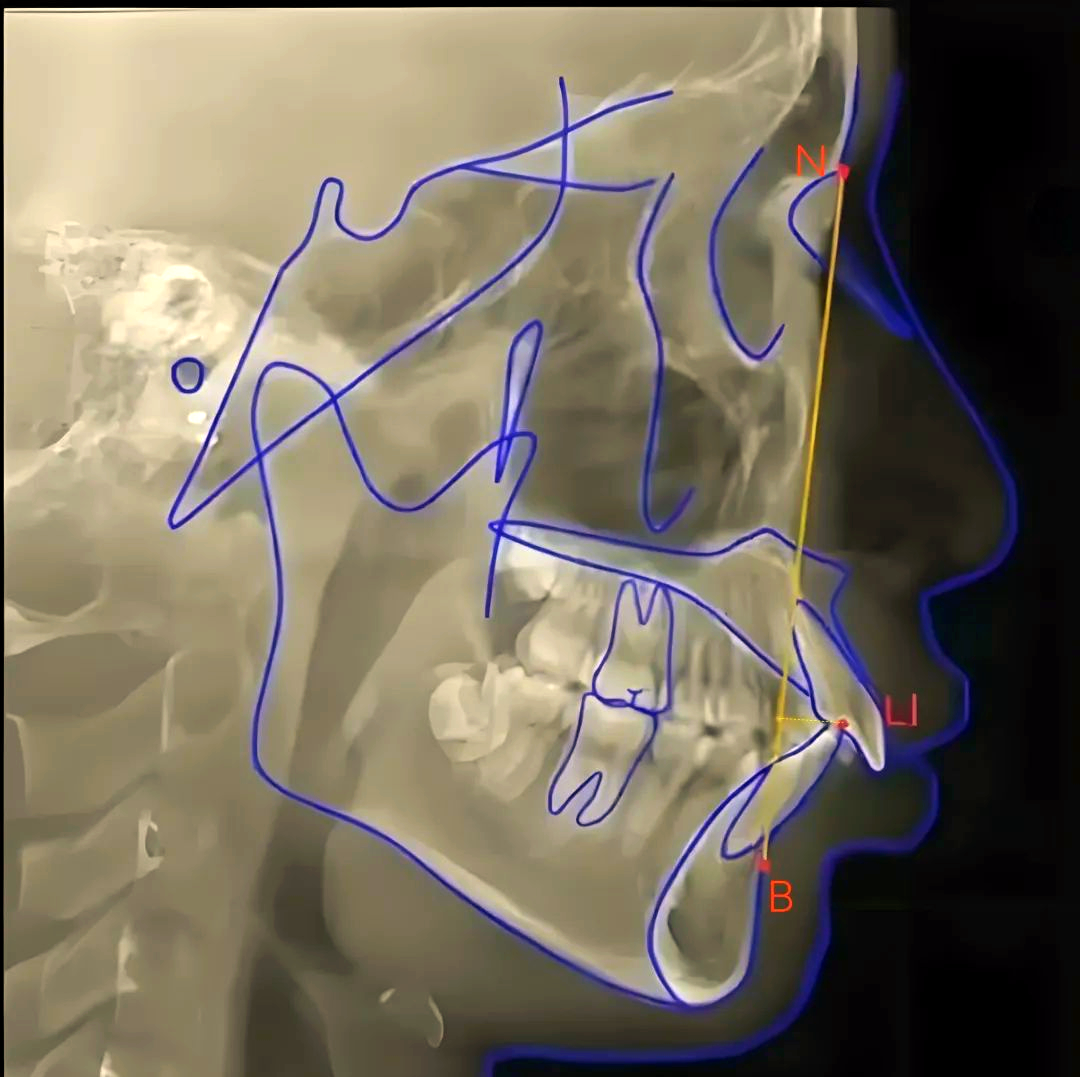

头影测量中如何准确找到标记点

图片尺寸1080x1048